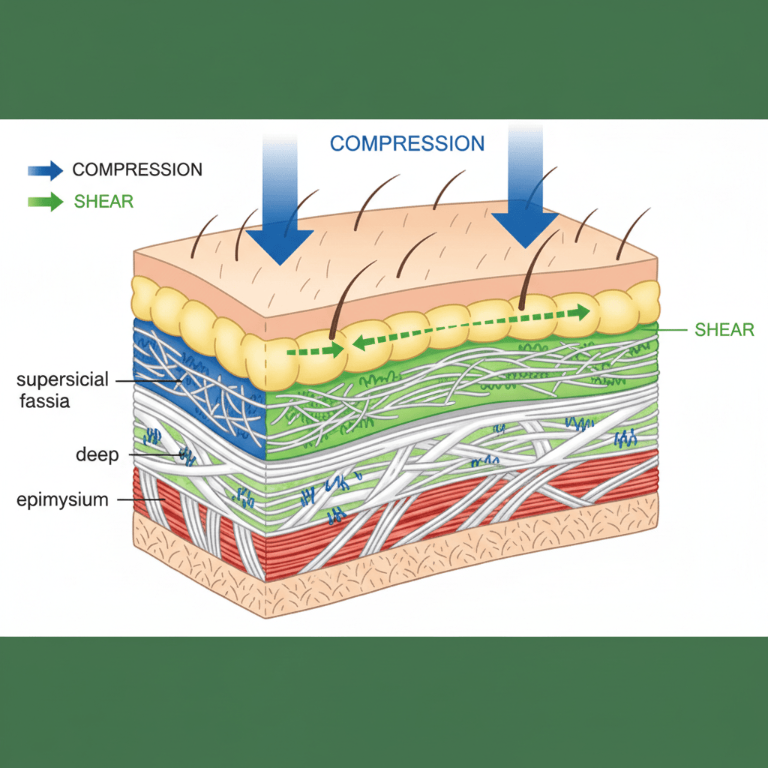

Our YD023 therapy gun combines two treatment approaches:

- Broad muscle relaxation (16mm amplitude)

- Precise fascial release (2mm 3D vibrations reaching 6-8mm depth)

This dual-action technology addresses both the large muscle groups and deeper fascial layers that contribute to plantar pain. Unlike traditional massage guns that only treat surface muscles, our 3D vibration technology penetrates to the inflamed fascia for more complete relief.

The plantar fascia absorbs shock during movement. Overuse, poor mechanics, or sudden increases in activity strain this tissue, causing microtears and inflammation at its weakest points.